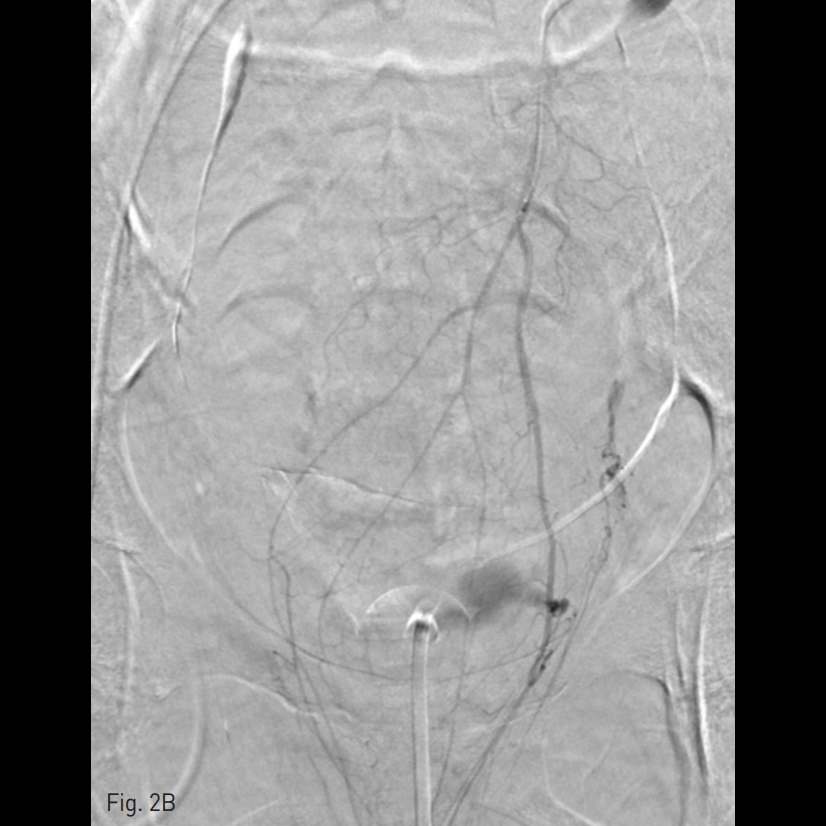

우측 총대퇴동맥을 천자하여 5 Fr sheath를 삽입하고, 5 Fr RUC catheter (Roberts Uterine Catheter, COOK medical, Bloomington, IN, USA)를 이용하여 좌측 내측 장골동맥을 선택하여 조영술을 시행한 뒤 좌측 자궁동맥을 선택하여 조영술 시행하였으며 (Fig. 1A), 출혈의심소견이 있어 gelfoam을 이용하여 색전술을 시행하였다 (Fig. 1B). 이후에 시행한 우측 내측 장골동맥을 선택하여 조영술을 시행한 뒤 (Fig. 1C), 우측 자궁동맥을 초선택하여 조영술을 시행하였을 때, 우측 자궁동맥이 비후되어 있어, gelfoam을 이용하여 색전술을 시행하였다. 색전술 직후 산부인과 진찰에서 지속적인 출혈소견이 보였다. 이에 5 Fr pigtail catheter를 이용하여, 대동맥 조영술을 시행하였다. 하장간막동맥 (Inferior mesenteric artery)으로 부터 출혈 소견이 관찰되었다 (Fig. 2A). 이에 대해서 2.2 Fr 마이크로카테터 (Progreat, Terumo, Japan)를 이용하여 하장간막동맥을 초선택하여 코일(Nester microcoil, COOK Medical, Bloomington, IN, USA)과 gelfoam (Spongostan, Ferrosan Medical Devices, Denmark)을 이용하여 색전술을 시행하였다 (Fig. 2B). 이후 다시 하장간막동맥 조영술을 시행하여 더 이상의 출혈이 없음을 확인하고 시술을 종료하였다 (Fig. 2C).

Fig. 1

A. Left internal iliac artery angiogram showed hypertrophied and left tortuous uterine artery.

B. Left uterine artery was complete embolization with gelfoam sponge

C. Right internal iliac artery angiogram showed hypertrophied and tortuous right uterine artery.

D. Right uterine artery was complete embolization with gelfoam sponge.